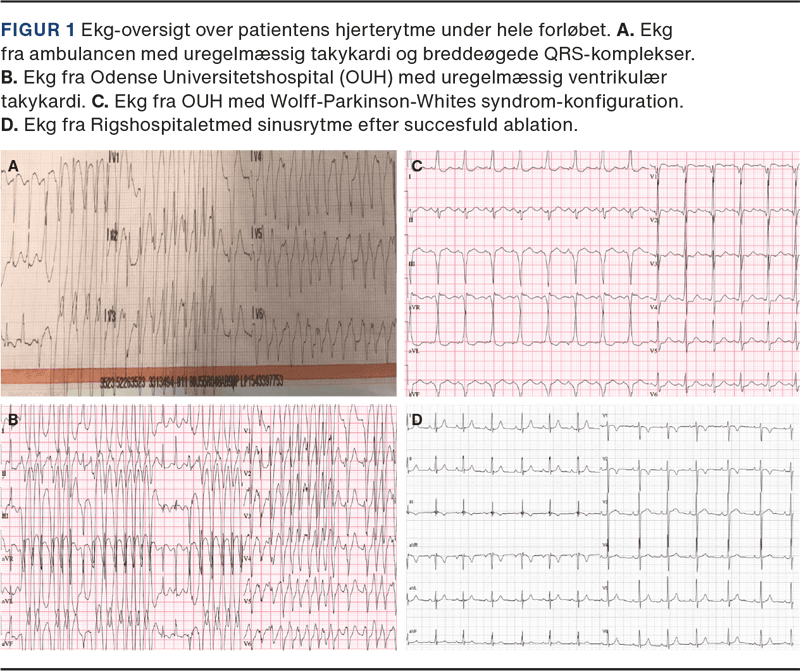

En tidligere hjerterask og asymptomatisk 11-årig dreng udviklede pludselig hjertebanken og besvimede kortvarigt. Ved ambulancens ankomst var drengen vågen, og på ekg’et sås uregelmæssig takykardi med breddeøgede QRS-komplekser (Figur 1A). Kort efter ankomsten til Odense Universitetshospital udviklede drengen klinisk hjertestop. Ekg’et viste uændret uregelmæssig ventrikulær takykardi (VT)/VF (Figur 1B). Efter fire DC-stød, adrenalin 0,6 mg og amiodaron 300 mg opnåede drengen bærende cirkulation, angiveligt 4 min efter klinisk hjertestop. Drengen var fortsat bevidstløs med et laktatniveau på 9,8 mmol/l og pH på 7,14. Telemetri viste intermitterende, non-sustained, uregelmæssig VT/VF, og drengen blev overflyttet til Rigshospitalet i intuberet, sederet og kølet tilstand. Ekg’et viste sinusrytme med VPE/deltatak (Figur 1C), og man havde mistanke om, at drengen havde præexciteret AF. En ekkokardiografi (EKKO) viste strukturelt normalt hjerte med let nedsat venstre ventrikel systolisk funktion (LVEF). Efter 24 timers køling blev der i generel anæstesi foretaget elektrofysiologisk procedure (EPS) med ablation af en højresidig posteroseptal AP mellem højre atrium og ventrikel. Drengen havde efterfølgende ingen neurologiske symptomer, EKKO viste normaliseret LVEF, telemetri var uden arytmi, og ekg var uden VPE dagen efter (Figur 1D) samt efter ti ugers opfølgning.